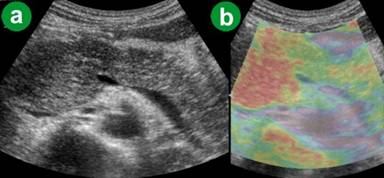

Chronic Pancreatitic Group (Group 2)

The ARFI-VTQ values for the pancreatic parenchyma ranged from 0.65 m/s to 1.74 m/s with a mean value of 1.240±0.235 m/s (Table 2; Figure 1). On eSie touch elastogram the pancreatic parenchyma and peripheral fat appeared light gray to gray (scores 2-3) on gray scale (Figure 3), while on the color scale it was yellowish green to yellow (scores 2-3; Figure 4).

Figure 3. Chronic pancreatitis. a. US B-mode image. b. eSie touch gray scale image (light gray to gray: score 2-3). |

Figure 4. Chronic pancreatitis. a. US B-mode image. b. eSie touch color scale image (yellowish green to yellow: score 2-3). |